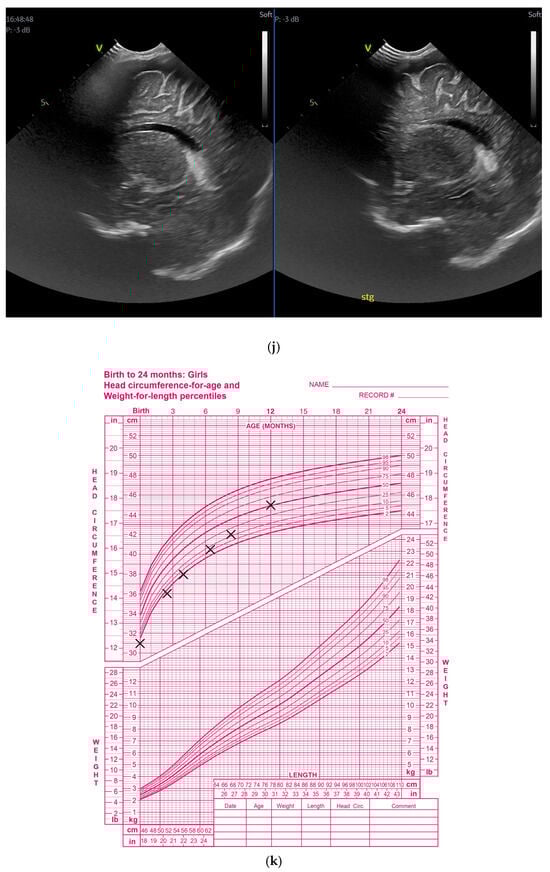

(a) Cranial ultrasound. Coronal view. Enlargement of the lateral ventricles with hyperechoic and third ventricle dilation. D1, D2—Levine index measurement. D3, D4—anterior horn width measurement. D5—third ventricle (personal image collection). (b) Cranial ultrasound. Sagittal view. Up—left ventricle. D1, D2—lateral ventricle measurements and thalamo-occipital horn width. Down—right ventricle. D1, D2—lateral ventricle measurements and thalamo-occipital horn width (personal image collection). (c) Cranial ultrasound. Sagittal view. Up—enlargement of the third and fourth ventricles. Measurements of the ventricles. Down—measurement of the resistive index (RI) performed on the anterior cerebral artery (ACA) using Doppler flow measurements. RI—0.74 (personal image collection). (d) Cranial ultrasound. Transtemporal view. Yellow arrow—enlargement of the Sylvian aqueduct (personal image collection). (e) Cranial ultrasound. Sagittal view. Yellow arrow—arachnoid cyst posterior to the third ventricle (personal image collection). (f) Cranial ultrasound. Coronal view. Lateral ventricles and third ventricle enlargement. D1, D2—Levine index measurement. D3, D6—right lateral ventricle measurement (anterior horn width). D4, D5—left lateral ventricle measurement (anterior horn width) (personal image collection). (g) Cranial ultrasound. Sagittal view. Left—left ventricle. D1—thalamo-occipital distance measurement. Right—right ventricle. D2—thalamo-occipital distance measurement (personal image collection). (h) Cranial ultrasound. Coronal view. Up—orange arrow—third ventricle. Red arrow—fourth ventricles. Yellow arrow—arachnoid cyst. Down—resistive index measured on the anterior cerebral artery. RI—0.79 (personal image collection). (i) Cranial ultrasound. Transversal view. Up—RI precompression value on the middle cerebral artery performed with Doppler examination. RI—68. Down—RI post-compression value on the middle cerebral artery performed with Doppler examination. RI—0.79 (personal image collection). (j) Cranial ultrasound. Up—coronal view. L1, L2—Levine index measurement of the lateral ventricles. Down—sagittal view. L1, L2—measurement of the thalamo-occipital distance (personal image collection). (k) Cranial ultrasound. Sagittal view. L1, L2—measurement of the third ventricle. L3, L4—measurement of the fourth ventricle. L5, L6—measurement of the arachnoid cyst (personal image collection). (l). Head circumference-for-age. “X” symbols represent the measurements performed from birth and follow-up examinations. Head circumference was still under the curve during follow-up examinations (personal image collection) [28].

The CUS examination performed at 48 h after birth showed increases in the diameters of all ventricles. The resistive index presented an increase as well. The bregmatic fontanelle started bulging. The dimensions of the Sylvian aqueduct were not modified (Figure 3f–h).

The CUS examinations performed at four days and seven days after birth showed stabilization regarding the values of the diameters. The pre- and post-compression values of the resistive index of the middle cerebral artery showed a delta-RI of 0.11 (pre—0.68, post—0.79, Figure 3i).

After discharge, at three weeks after birth (follow-up examination), the ventricle measurements showed wider ventricles and the arachnoid cyst was still present (Figure 3j,k).

The next follow-up examination performed a week later showed a delta-RI of 0.12 and an increase in the cranial perimeter (+ one cm since the last follow-up).

At 12 weeks of life (five week corrected age), ventricle dilations were still present. Neurological examinations showed axial and limb hypotonia. The general movement examination showed a poor repertoire with a General Movement Optimality Score (GMOS) of 19. At 18 weeks of life (11 week corrected age), the neurological exam revealed that the infant presented plagiocephaly and could keep eye contact, and during the traction-to-sit maneuver showed hypotonia of the neck muscles. In the prone position, the infant was unable to hold the head up. The passive tone assessment showed the “scarf sign”, with the elbow at the midline bilaterally and a popliteal angle of 90° on the right and 110° on the left. Deep tendon reflexes were present. The general movement (GM) assessment revealed absent fidgety movements, with a Motor Optimality Score (MOS) of 13.